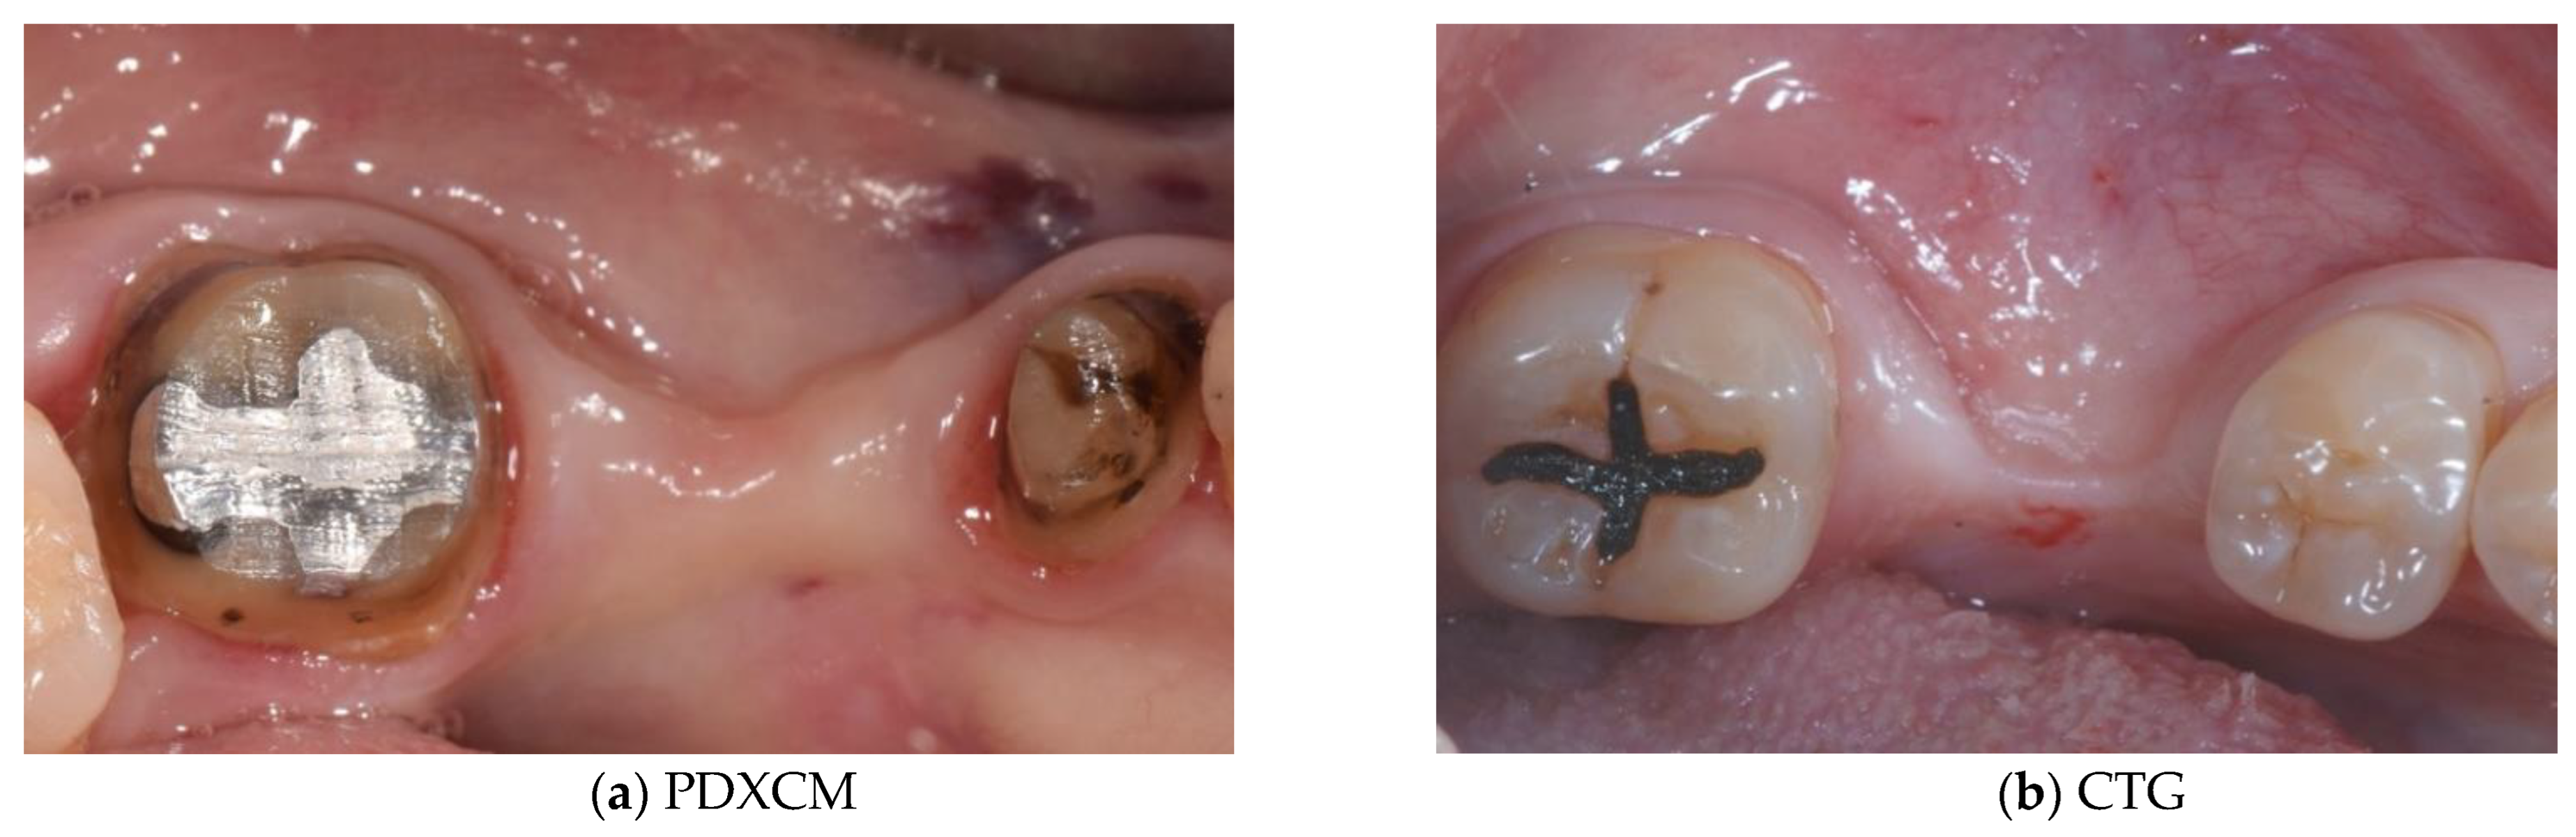

4. Discussion

5. Conclusions